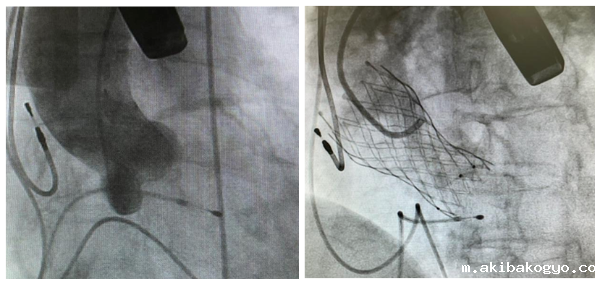

经过术前的精确评估,在多学科团队协同下,姚启恒教授(右)、陈良贵医生(中)、曹高镇医生(左)正在为曾阿姨进行TAVR手术。

术中的精准操作,瓣膜释放定位及膨胀形态良好,研判后决定不行烟囱支架,避免了冠脉支架的植入。

主动脉瓣造影&瓣膜完成释放

姚启恒教授介绍说:“术前评估患者瓣叶明显增厚,左右冠窦部分粘连,法式窦结构不大。术中左冠开口闭塞高风险,团队预先行冠脉保护,主动脉弓降部走行接近直角,过弓可能遇到其他意外困难,很考验术中精准操作。”